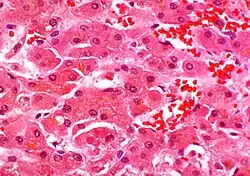

Ciałka Mallory’ego – kwasochłonne cytoplazmatyczne wtręty komórkowe, występujące w hepatocytach. Są to nieregularne skupienia włókienek keratynowych i innych białek (filamentów pośrednich) przypominające „kupkę siana”. Ujawniają się w wątrobie wraz ze stłuszczeniem od kilku godzin do kilku dni po nadużyciu alkoholu, ale rzadko występują gdy nie było jego nadużycia.